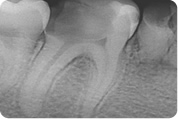

Sam postupak endodontskog liječenja započinje postavljanjem dijagnoze kliničkim pregledom i rtg snimkom. Rtg snimanje je obavezno prije samog liječenja jer se njime vide uzroci bolesti, postojanje eventualnog procesa u kosti te ono što je jako važno za samo liječenje, broj korjenova i kanala, zakrivljenost i druge njihove morfološke varijacije. Time se doktoru dentalne medicine omogućuje orijentacija u prostoru korijenskih kanala. Na osnovu rtg snimke doktor dentalne medicine može ocijeniti postoji li uopće mogućnost liječenja te predvidjeti moguće poteškoće u postupku.

Slijedeći korak je prikazivanje endodontskog prostora tj. "otvaranje zuba" tijekom kojeg doktor dentalne medicine uklanja ostatke upaljenog ili nekrotičnog tkiva i pronalazi korijenske kanale. Ukoliko je pulpa vitalna, tj. živa, područje se prethodno anestezira jer je zahvat u protivnom jako bolan. Potom slijedi instrumentacija korijenskih kanala pri čemu doktor dentalne medicine tankim iglicama ulazi u kanale. Njima se uklanjaju ostatci tkiva i detritusa, čiste i šire korijenski kanali po pravilima struke.

Kanal se širi iz razloga da se olakša uklanjanje nepoželjnog sadržaja te da se isti može hermetički napuniti. Kad je kanal pripremljen, puni se gumastim materijalom ( štapićima ) i cementom.

Nakon završenog liječenja, kvaliteta punjenja se provjerava rtg snimkom čime se procjenjuje dužina i kompaktnost punjenja. Tek ako je rentgenogram potvrdio dovoljno kvalitetno punjenje, zub se rekonstruira bilo ispunom ( "plombom" ) ili protetski ( nadogradnja i krunica ).